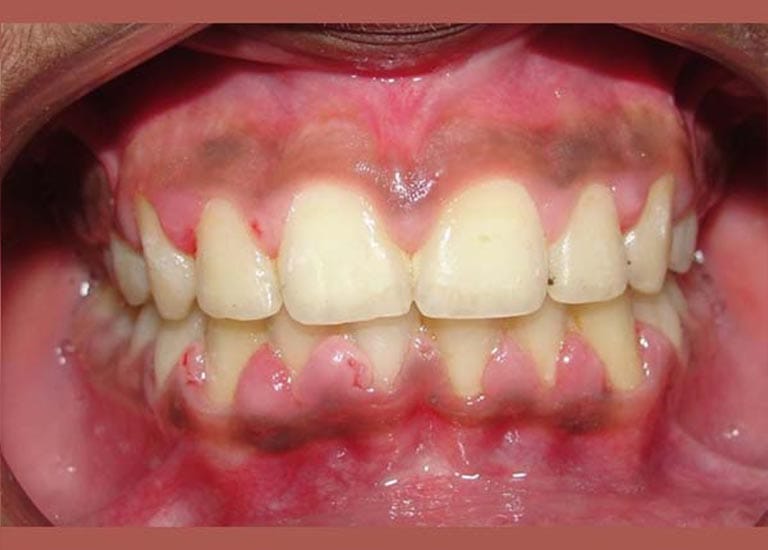

عانى هذا الشاب اليافع من بروز شديد في الأسنان وصل إلى 1 سم، وكان سببه الرئيسي هو تراجع الفك السفلي، وهو ما كان يظهر بوضوح على بروفيل وجهه الجانبي.

كما تظهر الصور، كان التحسن جذرياً ليس فقط في الابتسامة ولكن في تناسق ملامح الوجه بالكامل. تم تصحيح البروز، وتحسنت علاقة الفكين، وحصل الشاب على ابتسامة جميلة وواثقة.